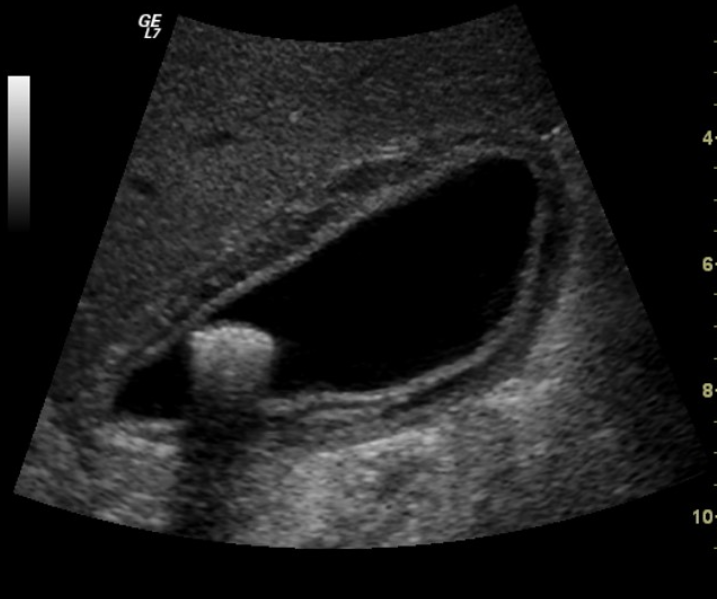

Acoustic Shadowing

occurs at interfaces that reflect and/or absorb a significant portion of the U/S beam

common with mineral interfaces (bones, calculi, foreign bodies)

Edge Shadowing

most common with round fluid filled structures

occurs at edge parallel to the sound beam

causes a dark shadow from edge of structure

gallbladder, urinary bladder, cysts, and sometimes kidneys

Acoustic Enhancement

increased echogenicty of tissue deep to an area or structure

often seen deep to fluid filled structures